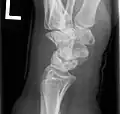

X-ray showing stage IIIB on right wrist, with ulnar impingement. -